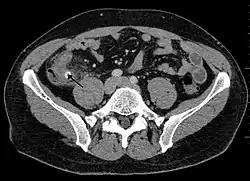

![]() حصاة برازية مشاراً إليها بالسهم والتي تسببت بالتهاب في الزائدة الدودية. حصاة برازية مشاراً إليها بالسهم والتي تسببت بالتهاب في الزائدة الدودية. | |

أشعة مقطعية تُظهر حصاة برازية.